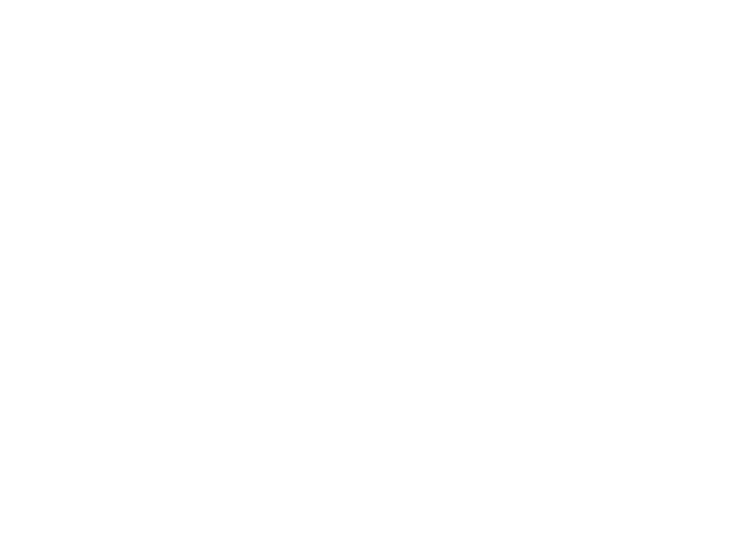

관절클리닉

관절클리닉

어깨통증, 무릎통증, 팔꿈치통증, 수부질환, 족부질환

비수술치료 클리닉

비수술치료 클리닉

도수/물리치료, 운동치료, 수액클리닉

척추클리닉

척추클리닉

목통증, 허리통증

비만통증클리닉

비만통증클리닉

체형 진단 및 운동치료

족부클리닉

족부클리닉

맞춤형 발진단 및 깔창제작